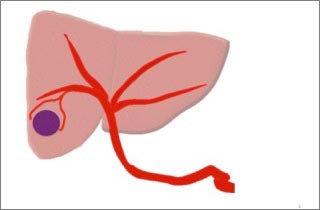

図3

腫瘍は縮小。